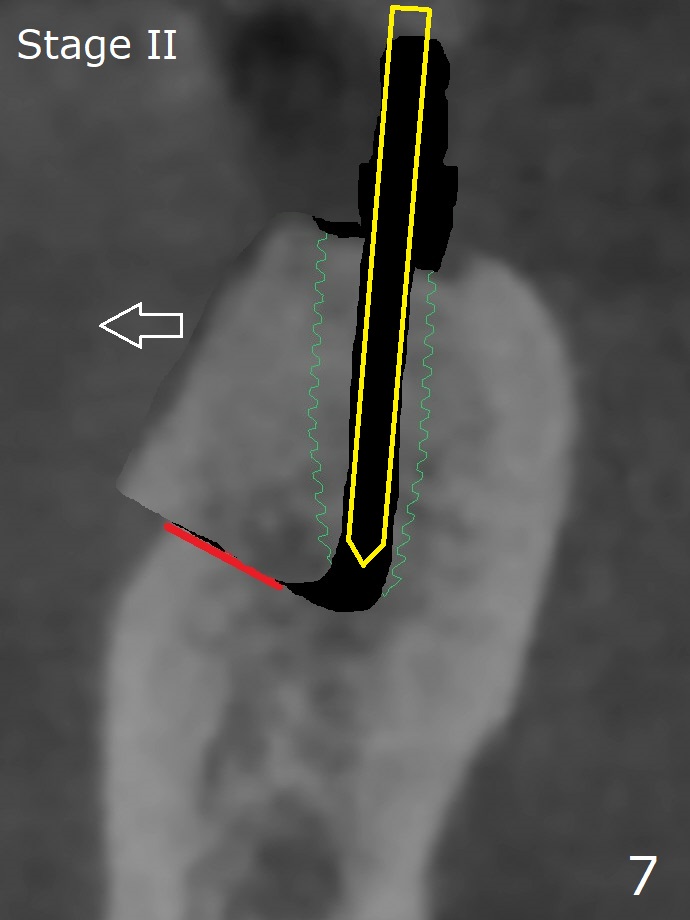

Several months post #31 socket preservation, the narrow ridge of #30 (Fig.1 (CT 3-D occlusal view), 6 (coronal section)) will be exposed with a crestal and 2 oblique incisions, followed by osteotomy with a 2 (2.2) mm drill (green) and a surgical guide. A crestal transverse cut will be conducted using a surgical fissure bur (Fig.2 red), followed by 2 vertical cuts (Fig.3,4 (3-D X-ray mode, buccal view) and an apical transverse one (Fig.5,6). The incision will be closed. Three weeks later, a crestal incision will be made. The buccal plate will be fractured and pushed buccal (Fig.7,8 arrow) using chisel (yellow). The guide will be reseated for osteotomy, implant placement (Fig.9 green) and bone graft. In fact there is not much problem when the osteotomy moves lingual.